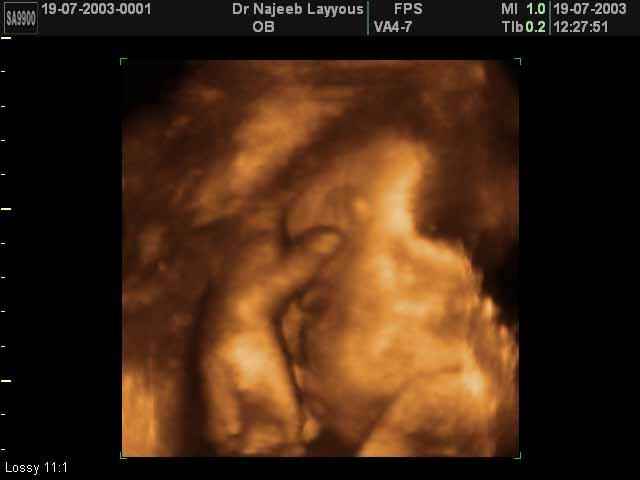

- 3D Fetal Profile Ultrasound Scan Photos